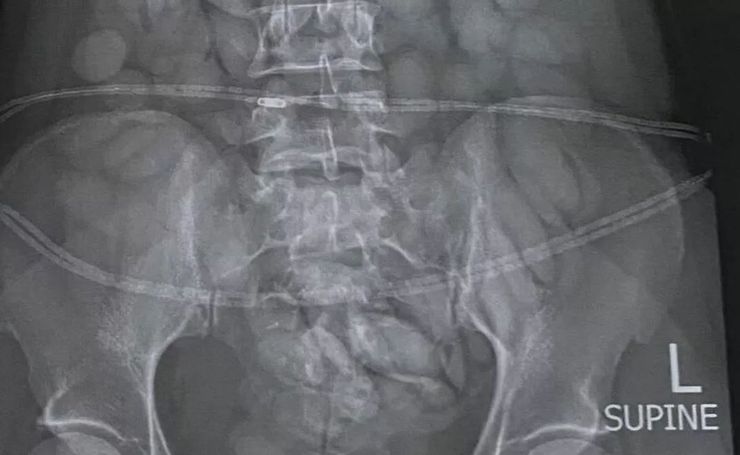

Пасажирку доставили до місцевої лікарні, де медичний рентген підтвердив наявність в її організмі низки сторонніх предметів.

Вивчивши рентгенівський знімок, зроблений інспекторами на лінії контролю, офіцери вилучили зі шлунку підозрюваної пакет із забороненими наркотичними речовинами.

Жінку негайно заарештували й доставили до місцевої лікарні, де медичний рентген підтвердив наявність сторонніх предметів в її організмі. Наразі фахівцям вдалось вилучити понад 60 кульок, ймовірно, з кокаїном.

Рентген підтвердив наявність сторонніх предметів в організмі пасажирки